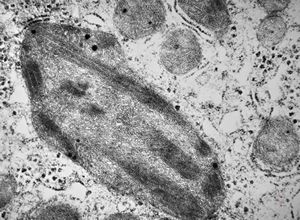

M,1y. | unusually cup-shaped mitochondria - plexus papilloma

M,1y. | intramitochondrial inclusion - plexus papilloma